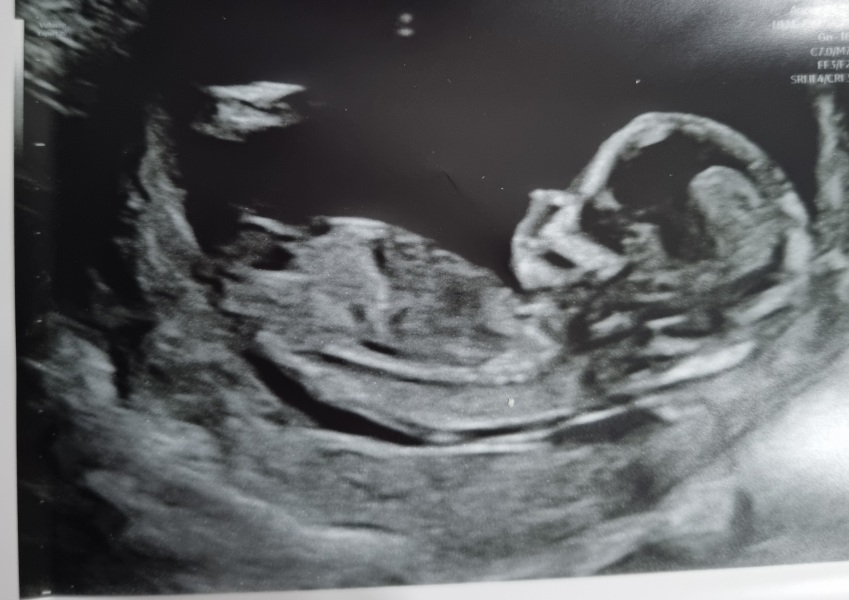

Can someone guess gender pls

Looks like a girl but not sure

This looks similar to my girl 🩷 scan